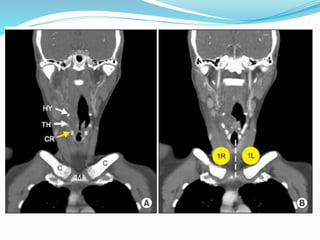

Station 1

 Low cervical, supraclavicular and sternal notch nodes

 Upper border : Lower margin of cricoid cartilage

 Lower border : Clavicle bilaterally and in midline upper

border of manubrium

Station 1  Lowcervical, supraclavicular and sternal notch nodes  Upper border : Lower margin of cricoid cartilage  Lower border : Clavicle bilaterally and in midline upper border of manubrium